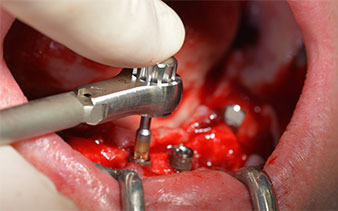

The mental foramen was first identified as a limiting anatomical structure and then the cortical bone of the crest was smoothed with the straight handpiece and a large rose-head bur (Fig. 4).

The surgical protocol for the implants employed (SKY, bredent medical) specifies a speed of 1,200 rpm for the pilot drilling (Fig. 7 - 9).

This corresponds to the next preset position in the Implantmed. Here we see the W&H contra-angle handpiece being held at a 45° angle to mesiocaudal in the region of 45 in order to preserve the mental nerve. The mental foramen is used as the anatomic reference for all drilling in this region. The subsequent holes were drilled at a reduced speed of 300 rpm (Fig. 10 and 11).

The next programmed setting is already for placement of the implants. In our practice we usually employ a torque of 32 Ncm to place the implants (Fig. 12 and 13).

High primary stability is an absolute requirement for an immediate restoration. In order to achieve this, the hole was not tapped in this case. The W&H Implantmed drill unit used here is equipped with a suitable special mode for this, which can also be directly selected and is indispensable for many indications. The final revolutions when placing the implants exceeded the value of 32 Ncm and were performed by hand. In such cases, we recommend utilizing the implants’ self-tapping function and twisting the implants backwards and forwards several times. This allows the implant to approach the final position gradually without exerting excessive pressure on the bone (Fig. 14).